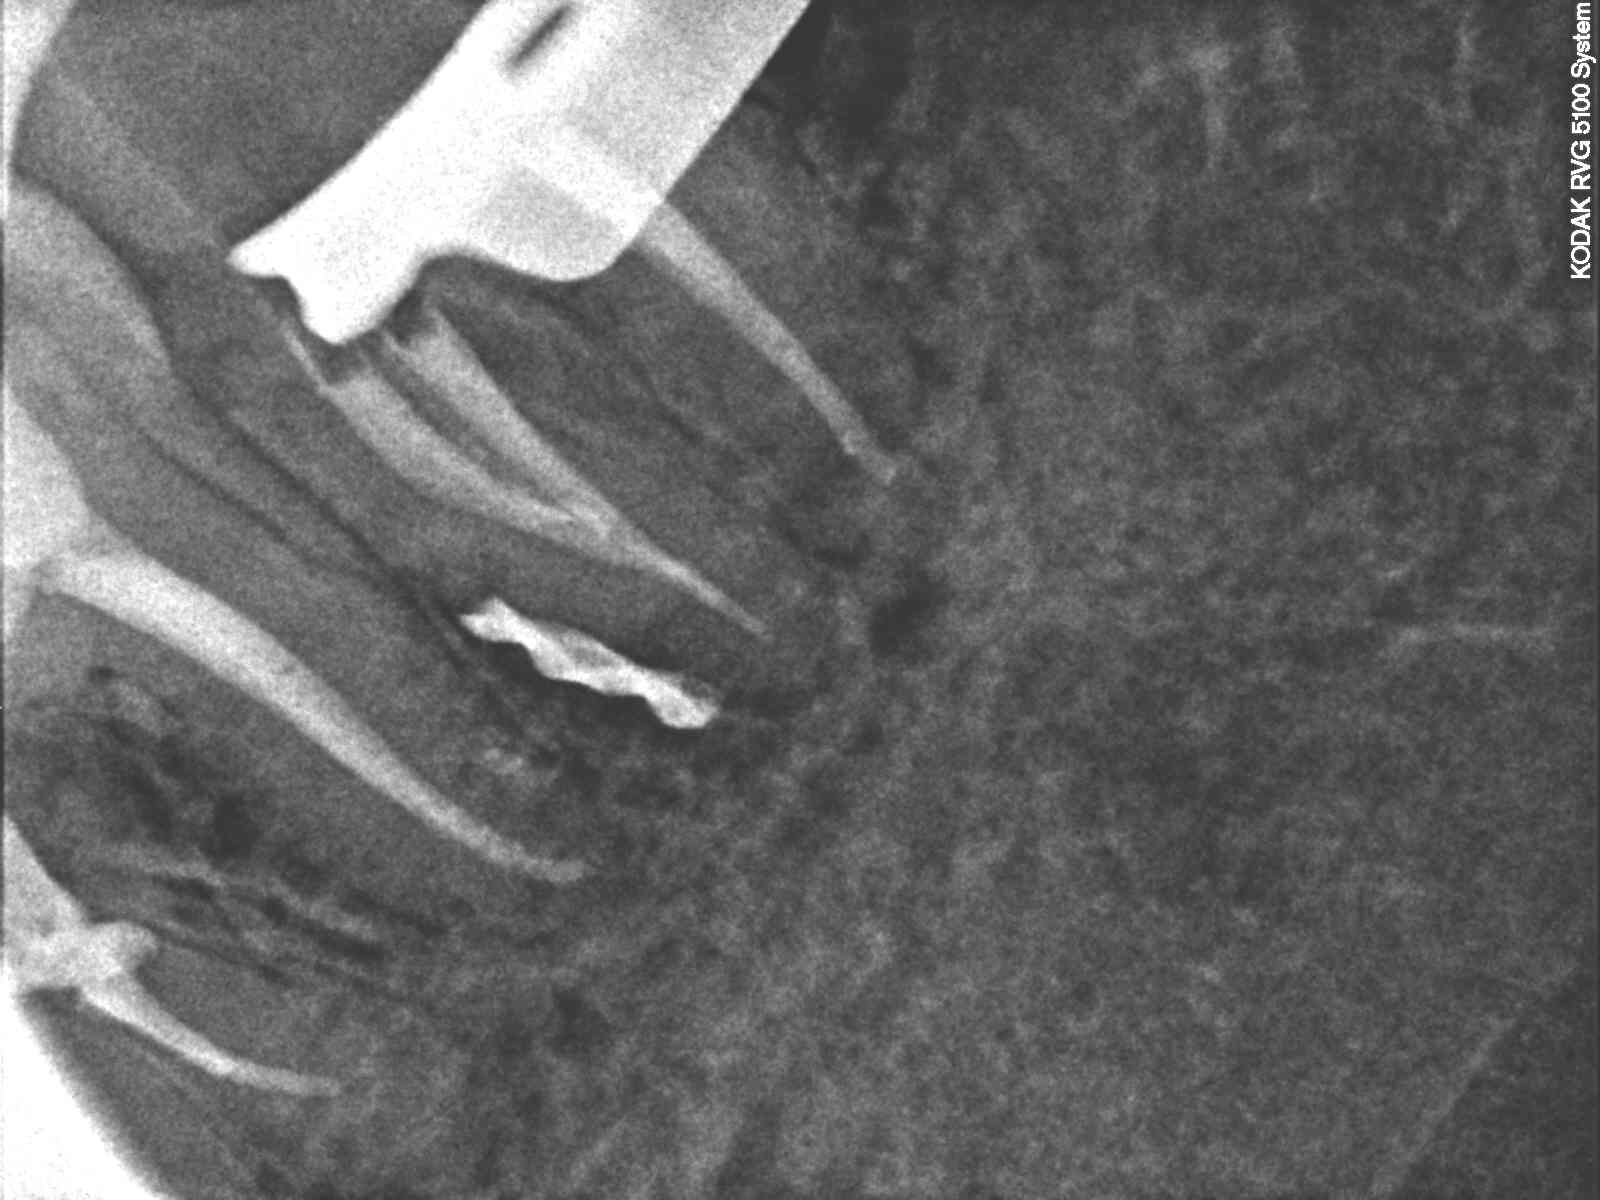

Ryc. 2. Zdjęcie rentgenowskie z narzędziami wprowadzonymi do kanałów bliższych po wcześniejszym usunięciu znajdującego się w nich materiału. Zostało wykonane w związku z trudnościami w ocenie długości roboczej kanałów metodą endometryczną i w celu oceny prawidłowości przebiegu preparacji. Brak możliwości wprowadzenia narzędzi na pełną długość spowodowany najprawdopodobniej wytworzonym podczas wcześniejszych prób leczenia endodontycznego stopniem w zębinie korzeniowej w miejscu łączenia się kanałów bliższych.